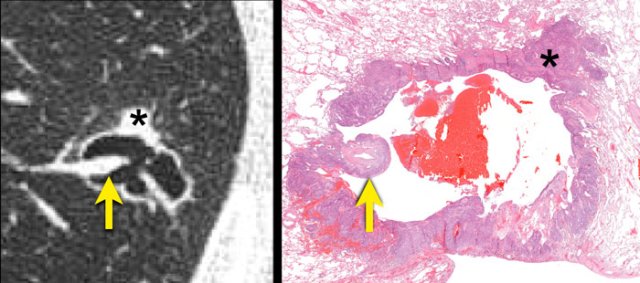

Radiologic-histopathologic correlation of a squamous cell carcinoma.

A cystic air space lined is by tumour cells (asterisk) most likely represents a dilated distal airway.

Check-valve ventilation due to more proximal airway narrowing by malignant cells and/or fibrosis is presumed.

A juxtaposed pulmonary artery with surrounding malignant cells projects into the lumen (arrow).